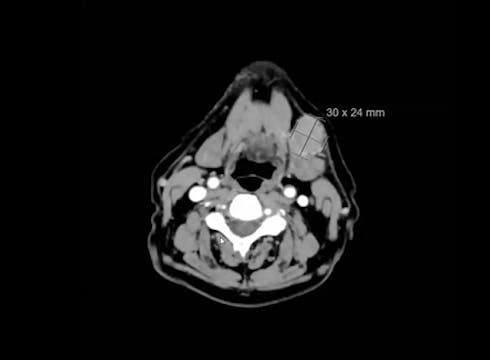

10/17/2023 - Dr. Kenneth Hu - Radiation Oncology - Head & Neck

nasopharynx, MRI, PET, CT, NPX carcinoma, balloon procedure, right nasal pharyngeal carcinoma, 2A node, microscopic disease, T1, CLL, right parotid mass, squamous cell, right superficial parotidectomy, modified neck dissection, right temporal skin lesion excision, lymph node, ECE, bolus, dissecte...